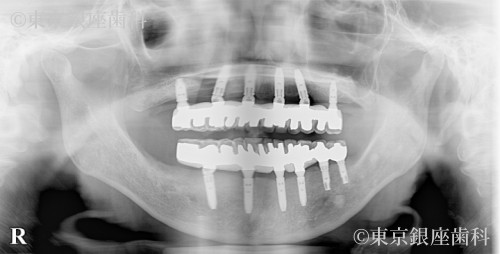

After

過去の高額ブリッジ治療が数年で崩壊し不安を抱えて来院。部分インプラント後、上下ワンデイへ移行。サイナスリフトも併用し安定した噛み合わせを獲得。

上下ワンデイインプラント+サイナスリフト